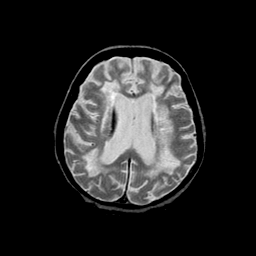

Basal Ganglia Calcification: T2-weighted MR -- Slice #11

[Home][Help][Clinical] Slice 11